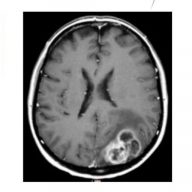

Targeting glioblastoma cells in tumour microenvironment combining irradiation with selective metalloprotease inhibitors